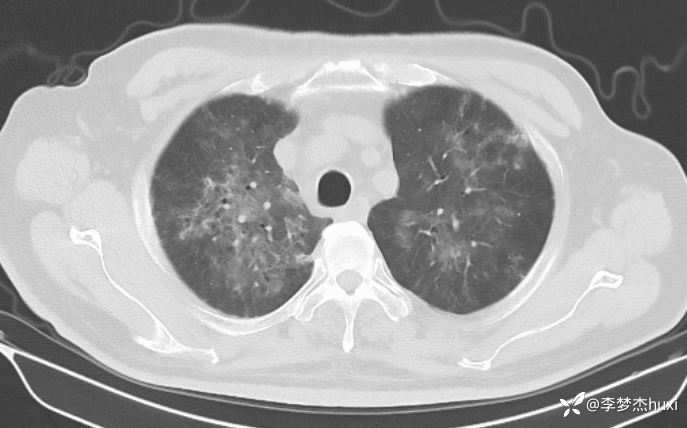

男性74岁,莫西沙星治疗加重的肺炎,可能什么病原菌?

既往史:既往高血压病史 20 余年,最高 180/90mmHg,平素口服降压零号治疗,控制可;糖尿病病史 20 余年,平素应用诺和灵 30R,控制良好;右肺鳞癌病史11月,放疗结束3天,期间放射性食管炎,目前仍吞咽痛;否认冠心病病史;否认“肝炎”、“结核”等传染病史;否认外伤史,否认手术史,无输血史,否认药物、食物过敏史;预防接种史不详,系统回顾无特殊。。

治疗经过:莫西沙星、喜炎平治疗进展

讨论:可能什么病原体?